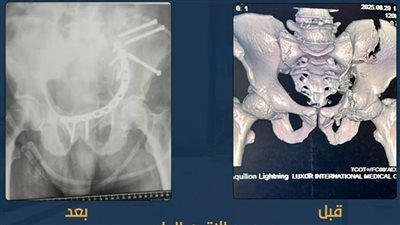

عظامه متفتتة.. نجاح عملية جراحية دقيقة لتثبيت كسور بالحوض لمريض بمجمع الأقصر الطبي الدولي